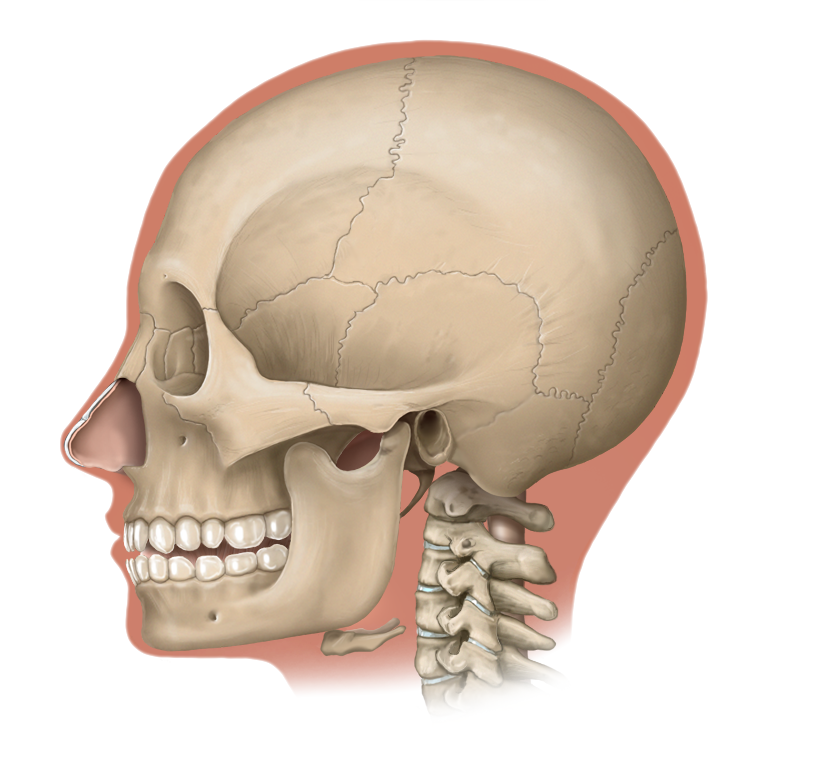

Medical Illustration

All images are works made for hire and are the exclusive property of the client. These are shown as sample purposes of my work only. For licensable work, please see my Illustration Services page.

Medical Illustrator for Precision Graphics, Lachina, and Human Kinetics Publishing (current)

Contract freelancer for many others, some examples of my work below.